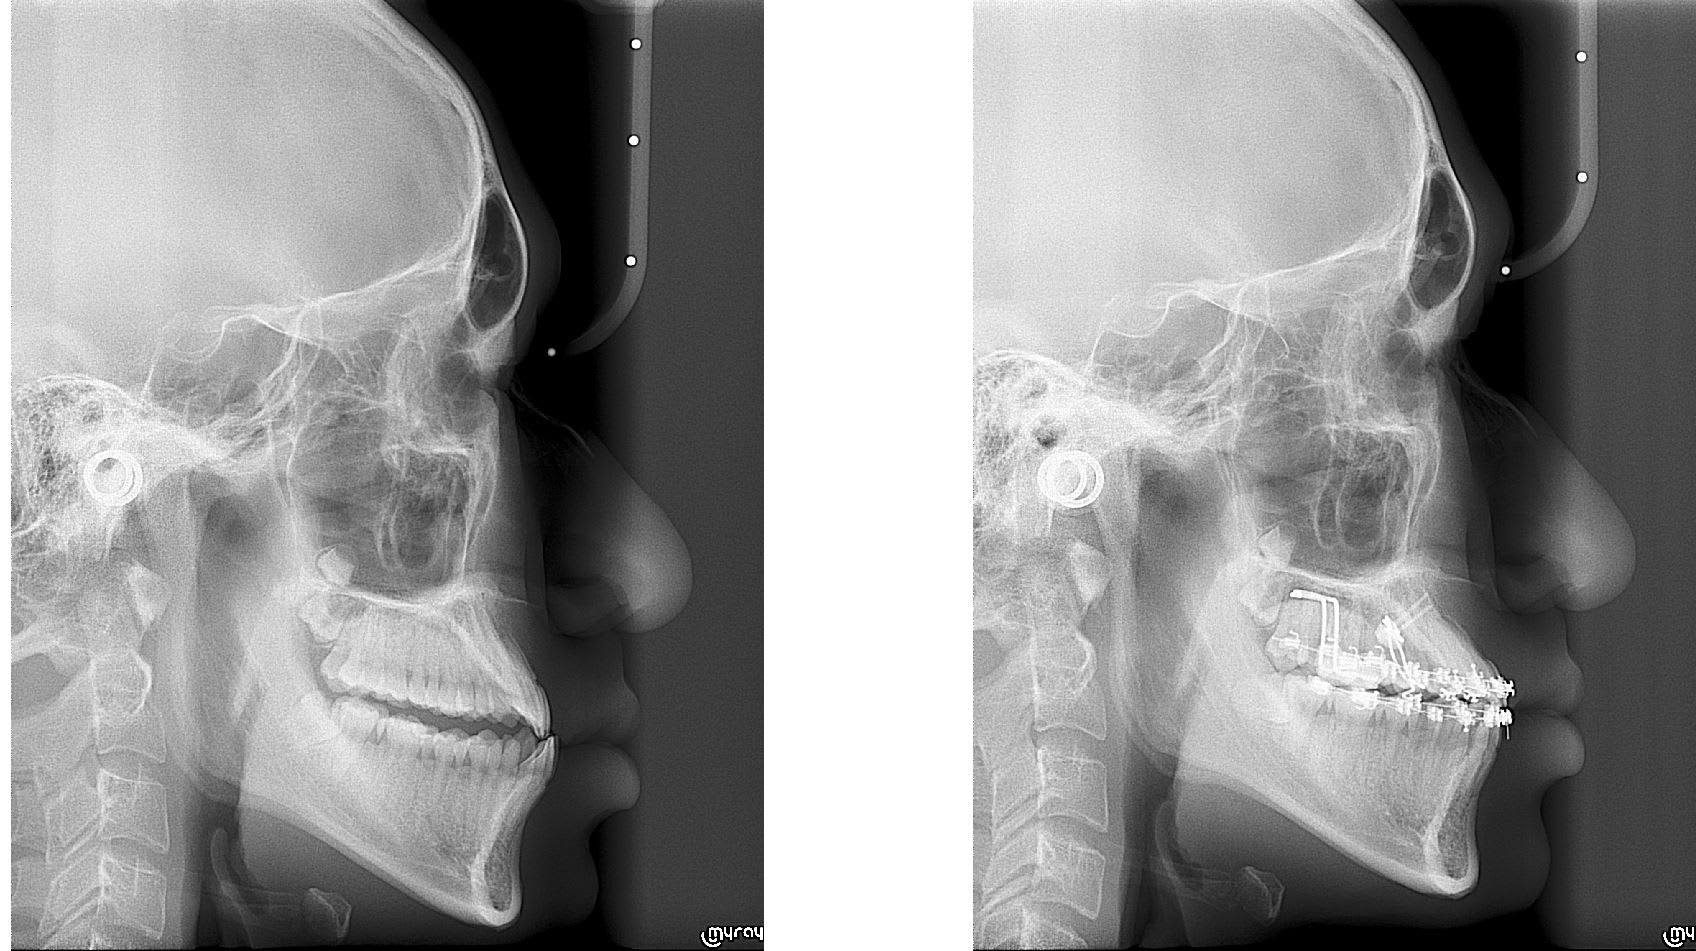

Deux patients vue Samedi dernier , deux cas un peut compliquer et un des deux ou je n'avais jamais vue de cas équivalent. Les deux sont en vois de finalisation pour la partie " hard "

Un cas de cross bite ( déjà montré ) postérieur pas le pire que j'ai eux mais ça reste quand même assez costaux.

Occlusion rétablie du coté cross bite et présque rétablie du coté " normal "

Un cas plus inhabituel Patient class III avec cross bite antérieur. Ici gros espaces en antérieur à la mandible. Vue le coté inhabituel j'ai fait un set up qui m'a indiqué qu'il fallait à la fois mésialer les secteurs postérieur supérieur et inférieure. Traduction pas de mécanique class III classique.

Pour la distalisation j'ai utilisé deux minivisse en palatin avec un fil de 0.8 mm en boucle. Le design est simple , économique , ne necessite pas de matos particulier ( important au Cambodge ) et est très efficace.

Quelque photo avant après. Les pano sont intéressante car elles montre bien que l'on à mesialé l'ensemble des secteurs post, que sa soit à la mandibule ou au maxillaire.